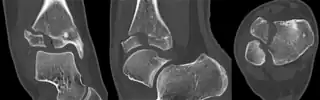

a,b)CT scan, coronal and axial plane of a Tillaux fracture in a male -

CT scan